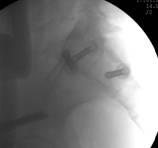

整个手术1小时内完成,通过术后CT影像证实3D打印导航模板引导骶髂螺钉置入安全、准确、创伤较小,手术时间短,患者也很快得到了较好的恢复。

术中C臂

术前CT和术后CT比较